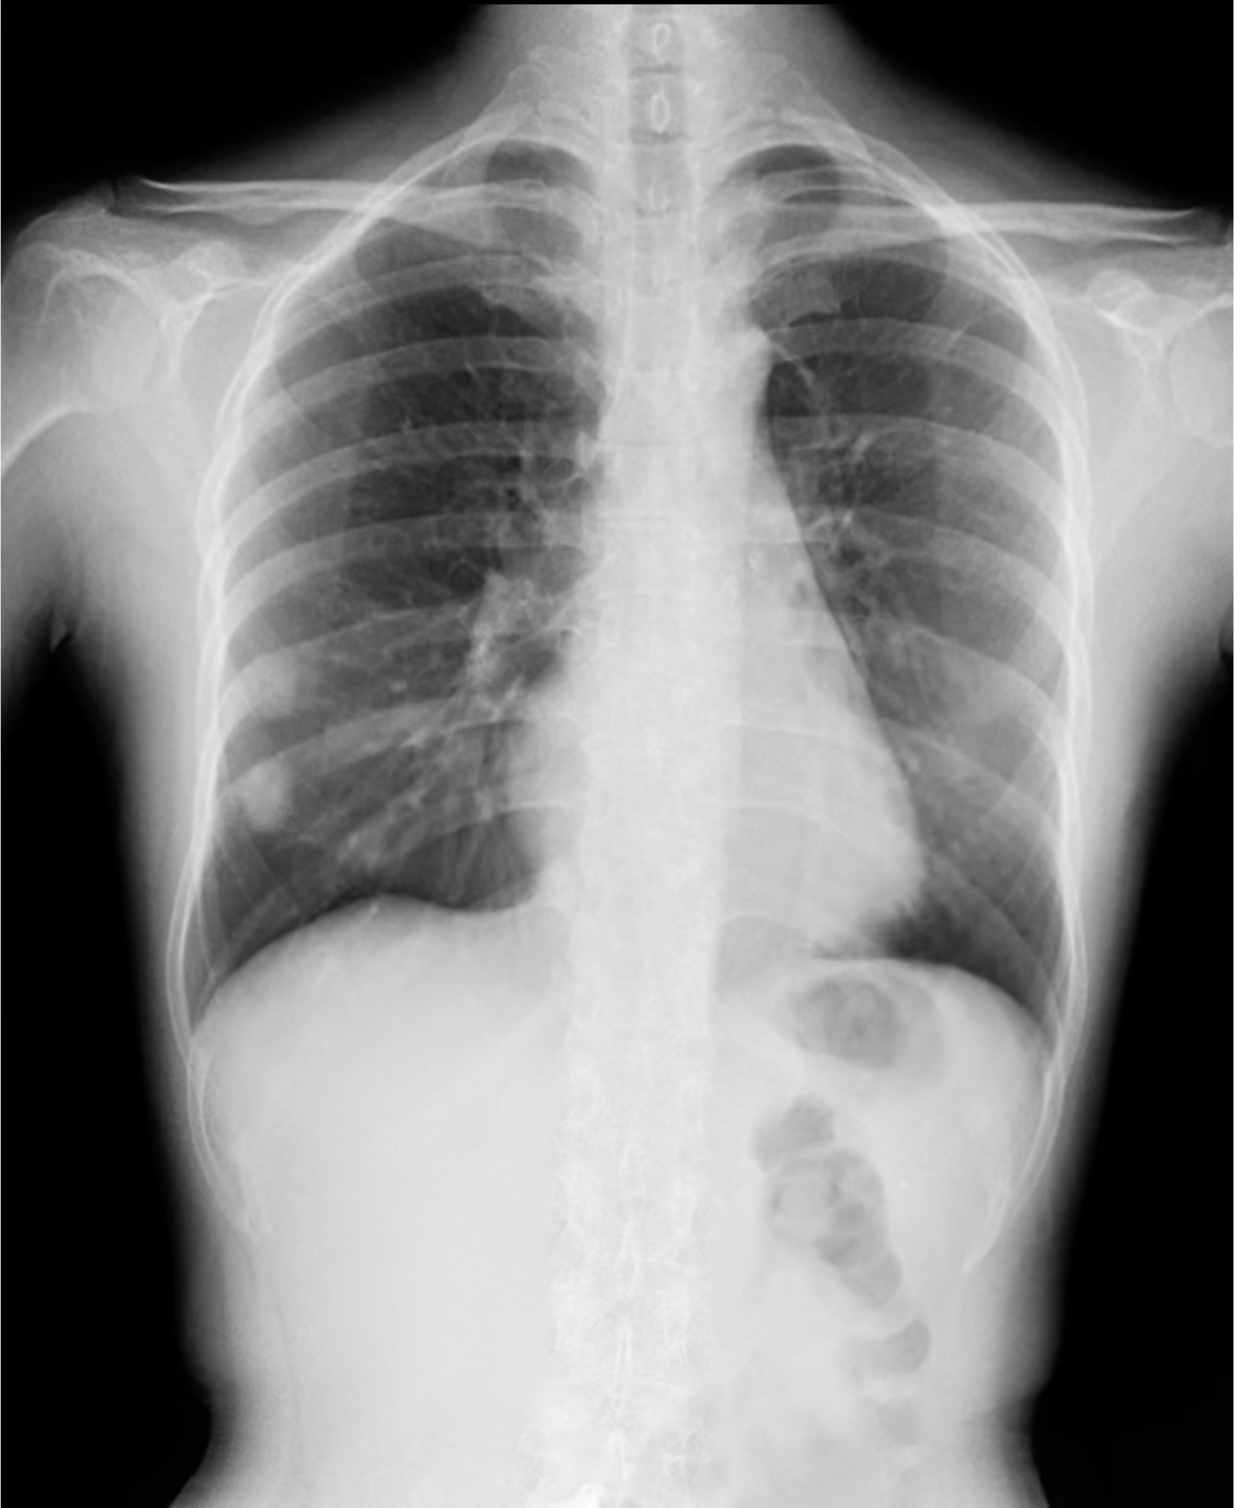

Dynamic Digital Radiography (DDR) allows you to observe movement like never before. This novel low-dose X-ray imaging technique enables visualization of anatomy in motion.

The DDR can acquire up to 15 sequential radiographs per second and play them back as a cine loop, allowing you to observe the physiological cycle and as individual radiographic images (up to 17″x 17″ in size). This advancement in digital X-ray technology is FDA-approved and available in many of our systems. DDR is X-ray that moves!